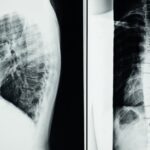

Comprendre la décompression spinale

La décompression spinale repose sur l’application de traction contrôlée qui permet de créer plus d’espace au sein du canal rachidien. Cette technique est particulièrement bénéfique pour ceux qui souffrent de maladies telles que la sténose spinale ou les hernies discales. En libérant les nerfs comprimés, la décompression permet d’atténuer la douleur, de réduire l’inflammation et de restaurer la fonction nerveuse, rendant ainsi le retour aux activités quotidiennes plus rapide et moins douloureux.

Cette méthode de traitement utilise des tables de décompression spécialement conçues qui intègrent des technologies avancées. Grâce à ces dispositifs, les professionnels de santé peuvent appliquer une traction contrôlée sur la colonne vertébrale, créant ainsi un espace entre les vertèbres. Cette action vise à réduire la compression nerveuse et à libérer les nerfs comprimés, permettant ainsi une amélioration significative des symptômes douloureux.

Enfin, il est essentiel de prendre en compte que chaque patient est unique et que les protocoles de traitement doivent être personnalisés en fonction de leurs besoins spécifiques. Des tables de décompression modernes, comme le modèle DPA Med, permettent d’intégrer des mouvements et des techniques adaptées à chaque individu, garantissant ainsi le meilleur résultat possible. Pour davantage d’informations sur comment la décompression spinale peut être bénéfique, consultez les ressources disponibles et envisagez de discuter de vos préoccupations avec un spécialiste.